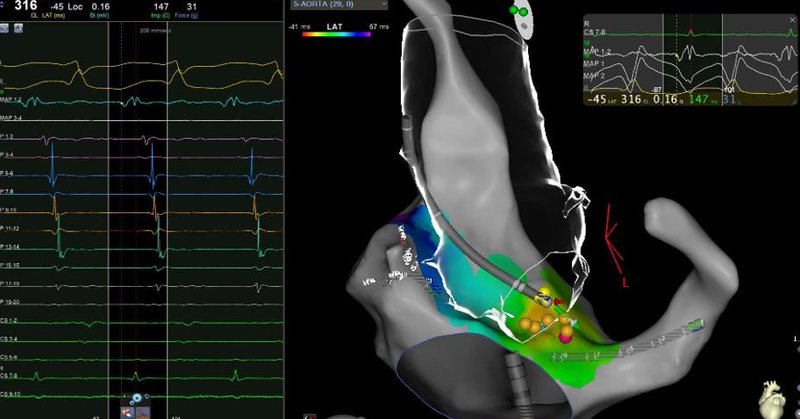

πŸš€New #BeatBoxBlog post! πŸš€ This week focuses on identifying intramural ventricular substrate! 1. Bipolar Vs Unipolar Voltage maps 2. ICE mapping 3. Cardiac MRI #epeeps #epfellows #foamed #meded #ecg #ablatevt #cardioed https://t.co/I3iN0zbq62

πŸš€ New #BeatBoxBlog Post! πŸš€ VT in 3D - and how Pacemapping can differentiate endocardial from intramural isthmus sites! https://t.co/qL5W9yeKcj #Epeeps #epfellows #ablateVT #foamed #ecg #ekg #meded #cardioed